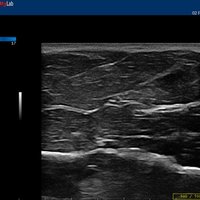

12”-Full-Touchscreen Farbdoppler

Das MyLab™One steht für das revolutionäre „Arm-held“ Hochleistungs-Ultraschallsystem mit 12”-Full-Touchscreen. Aufgrund seines geringen Gewichts und der Tragbarkeit kann es auch ohne Arbeitsfläche verwendet werden. Eine einzelne Person kann dieses Gerät aufgrund seiner einzigartigen Funktionen allein und selbstständig bedienen.

Der intuitive Touchscreen bietet dem Benutzer schnellen und einfachen Zugang zu allen Steuerungsfunktionen. Mit der beeindruckenden Bildqualität und einem kompakten Design wird MyLab™One zur idealen Ultraschalllösung am Point-of-Care.